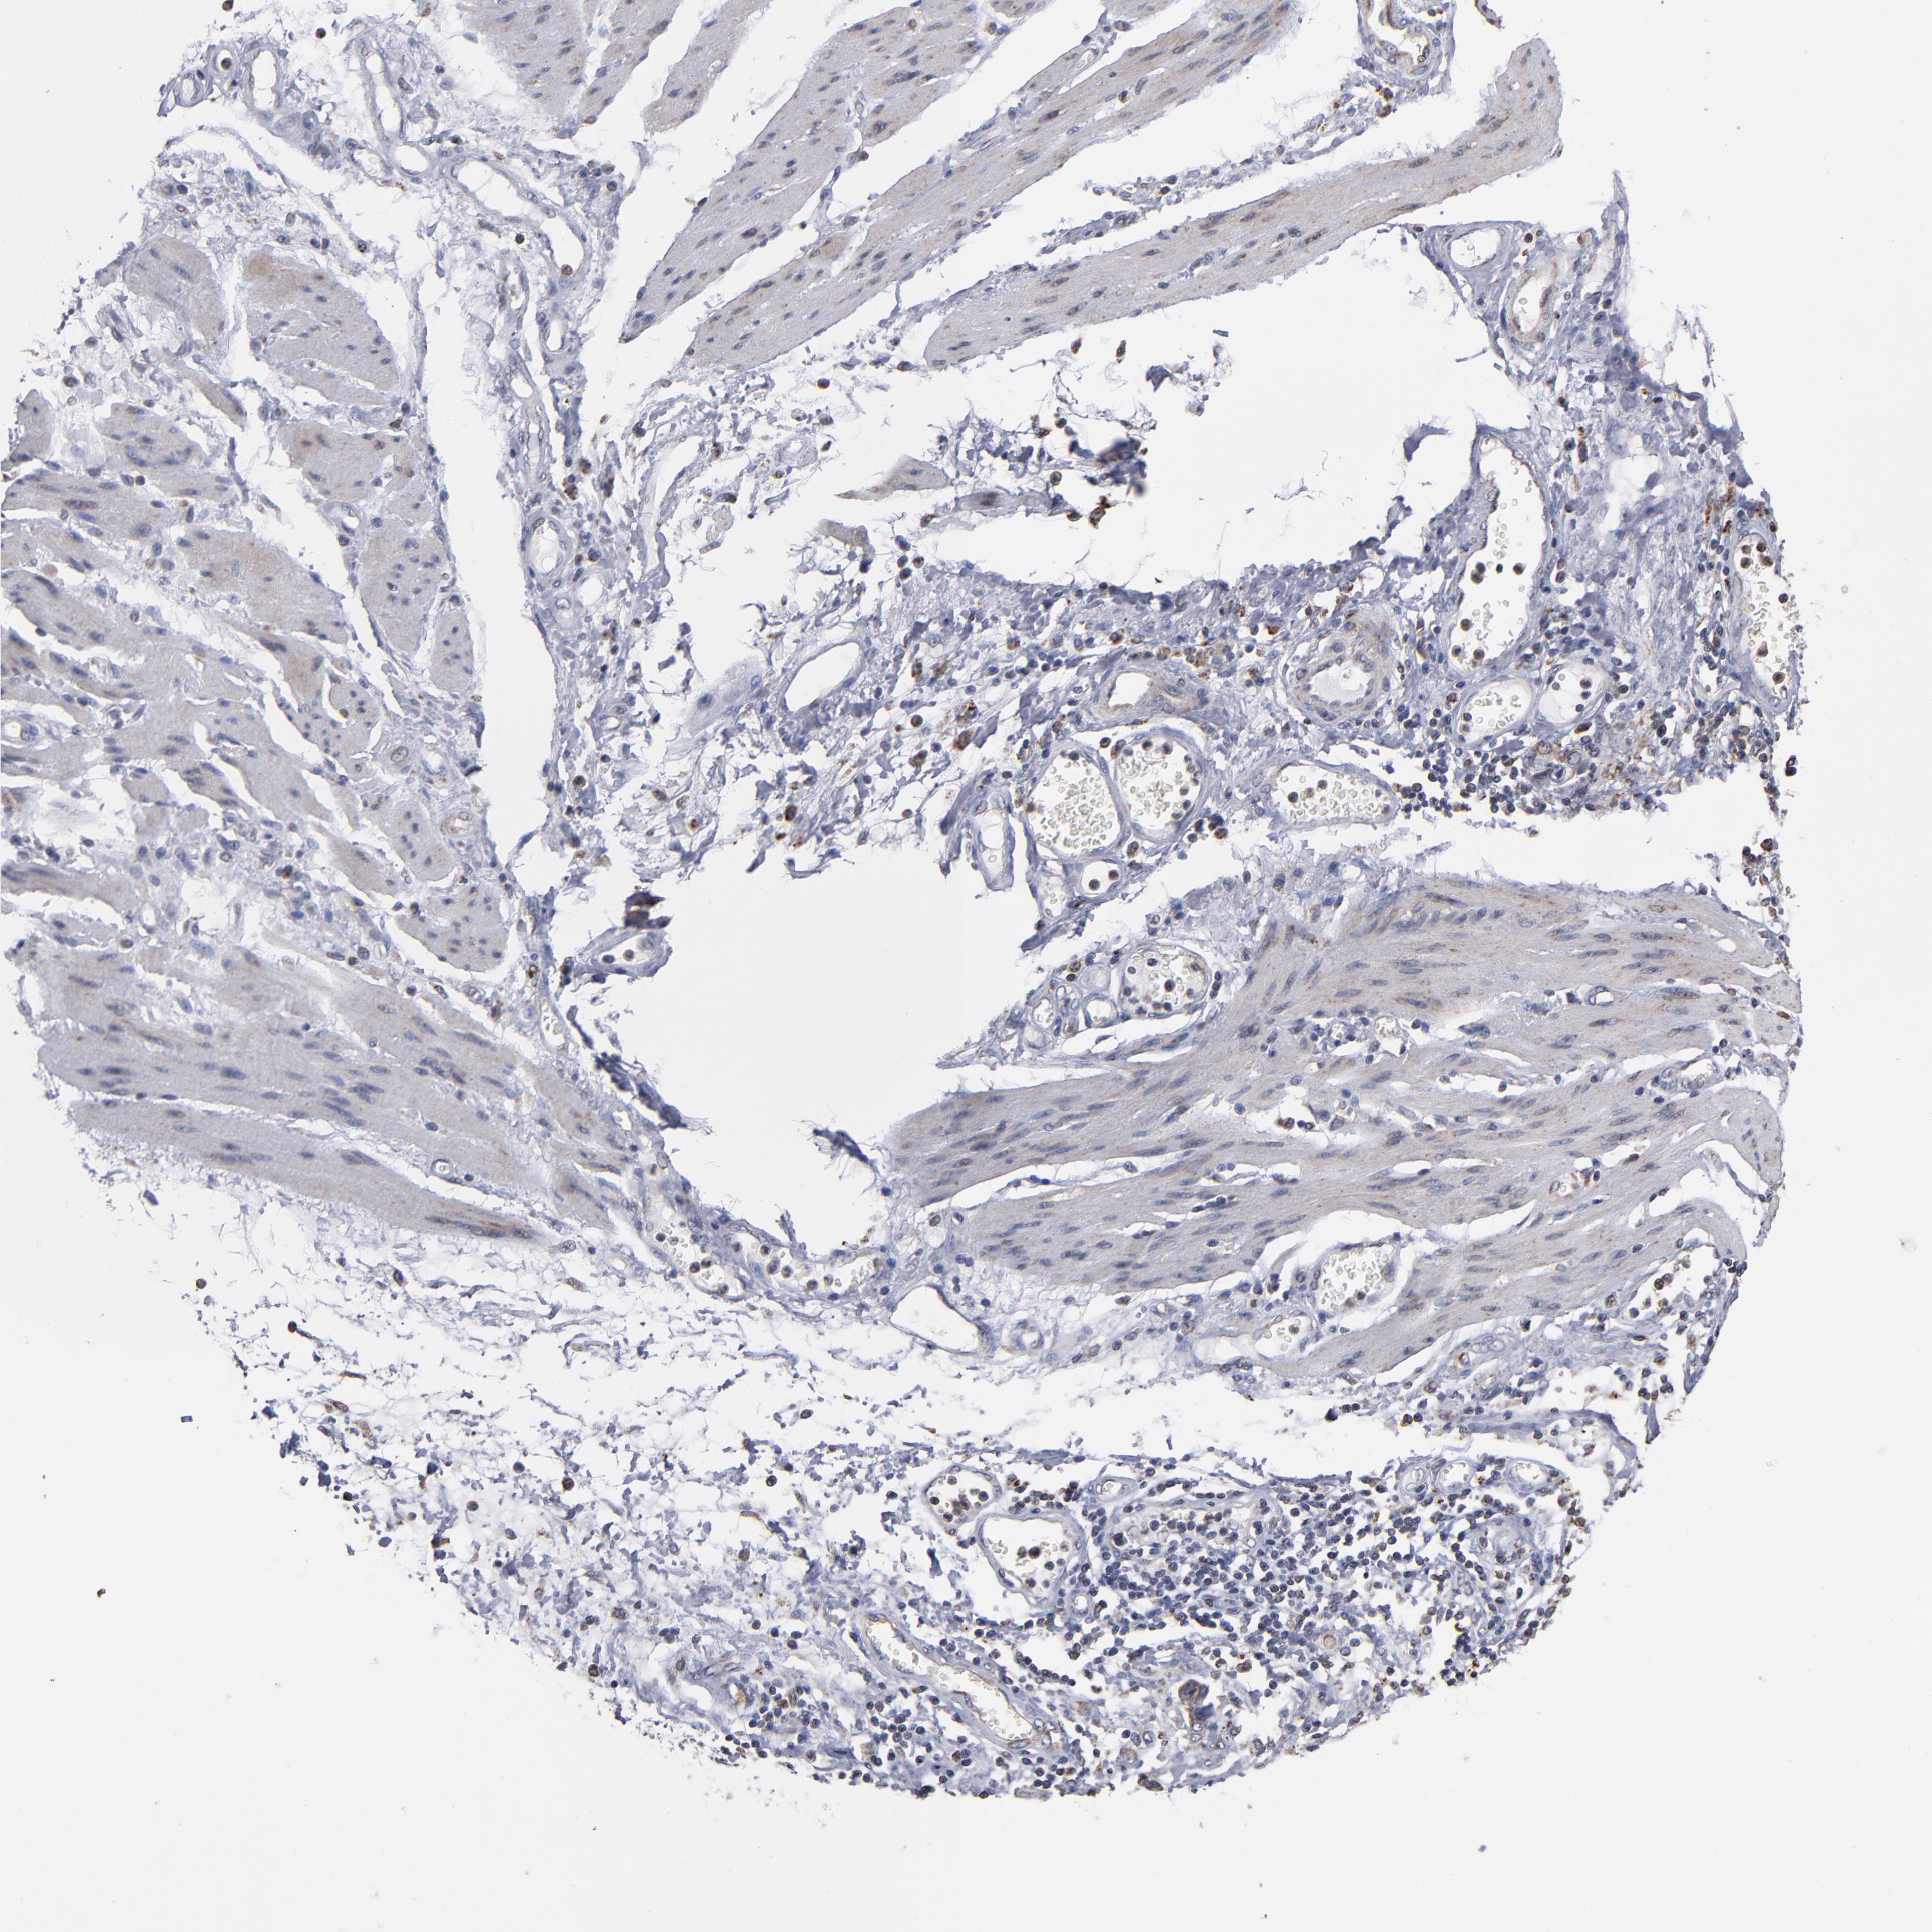

STOMACH CANCER - Protein expressioni

A mouse-over function shows sample information and annotation data. Click on an image to view it in a full screen mode. Samples can be filtered based on level of antibody staining by selecting one or several of the following categories: high, medium, low and not detected. The assay and annotation is described here.

Note that samples used for immunohistochemistry by the Human Protein Atlas do not correspond to samples in the TCGA dataset.

Antibody stainingi

Antibody staining in the annotated cell types in the current human tissue is reported as not detected, low, medium, or high, based on conventional immunohistochemistry profiling in selected tissues. This score is based on the combination of the staining intensity and fraction of stained cells.

Each image is clickable and will lead to virtual microscopy that enables deeper exploration of all samples and also displays staining intensity scores, fraction scores and subcellular localization as well as patient and tissue information for each sample.

Antibody HPA002893

Staining

High

Medium

Low

Not detected

Intensity

Strong

Moderate

Weak

Negative

Quantity

>75%

75%-25%

<25%

None

Location

Nuclear

Cytoplasmic/membranous

Cytoplasmic/membranous,nuclear

Adenocarcinoma, NOS